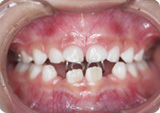

指しゃぶり(吸引癖)は乳児〜幼児前半ではほとんどの子供に認められます。

しかしこれが長期にわたっておこなわれると、咬合異常が形成されることがあります。

主なものとしては前歯部開咬(上下の前歯の間に隙間がある)、

上顎歯列の狭窄(上の歯列が狭くなる)があります。

また舌前突型嚥下(タングスラスト)も咬合異常に関係しておこります。

これは飲み込むときに舌が突き出されて上下の前歯の間に入り込む動作をおこなうものです。

頻繁に指しゃぶりをすることにより前歯が咬まない「開咬」等の咬みあわせの異常があるようなら、